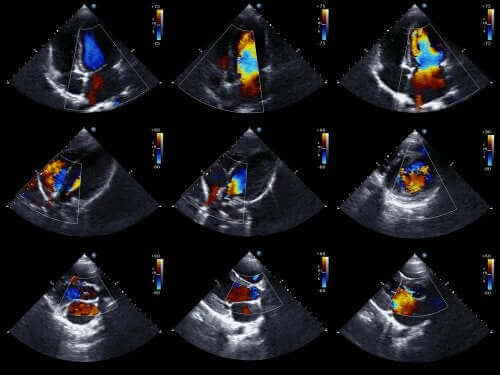

Sydämen ultraäänitutkimus on yksi tehokkaimmista tekniikoista sydämen synnynnäisten ongelmien diagnosoimiseksi.

Lääkärit pystyvät yleensä määrittämään tämän tyyppisen poikkeaman jo ennen kuin vauva syntyy. Tähän käytetään sikiön sydämen ultraäänitutkimusta, ja kyseessä on tekniikka jossa hyödynnetään ääniaaltoja, jotta saadaan luotua liikkuva sydänkuva.

Tämän menetelmän ansiosta pystytään näkemään sydämen piirteet ja tutkimaan sen toimintaa, kun vauva on edelleen kohdussa. Tällä tiedolla lääkärit voivat sitten valmistautua hoitoon heti syntymän jälkeen.